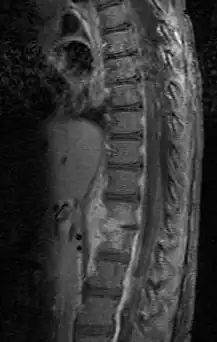

Diagnosis is usually apparent on MRI although plain X-rays and CT examinations can be suggestive. The MRI will reveal air changes in the disc and possibly even external involvement involving the bone or epidural regions. A biopsy may be performed and helps with diagnosis in some cases but often an organism is not obtained. C-reactive protein levels and ESR levels will be elevated and are useful for treatment. Often, the white blood cell count will be normal and the patient will be afebrile.

Discitis with anterior abscess (and disc space abscesses) -

An infected disc at the level of C5 C6 causing neurological symptoms